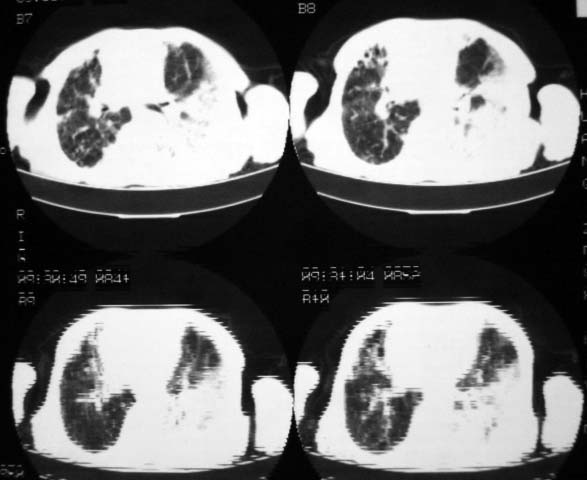

男,85岁,发热2月, 血常规:hgb99g/l.rbc2.55×1012/l.wbc3.8×109/l.n78.2%  l20.7% m1.1%.  hct26.3% .血沉20mm/hg.痰检结核杆菌阴性。ddp阳性。痰少粘稠色白。无咳血。

1.右上肺陈旧性肺结核灶;

2.左上肺、双下肺及右中叶肺炎(左上肺肺炎治疗后好转)

右上肺陈旧性肺结核灶,双肺感染灶〔大部份纤维化〕,肺气肿.

双肺继发型肺结核,肺纤维化,肺气肿,胸膜肥厚黏连。